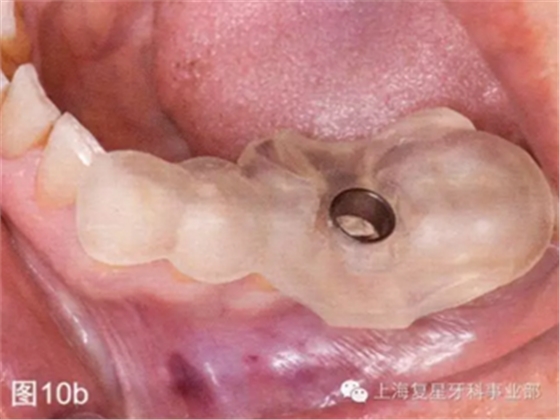

引導(dǎo)板一制作完成,就在模型上進行試戴,檢查其有無不密合的地方以及在對引導(dǎo)板和BioHorizons引導(dǎo)手術(shù)工具包消毒之前有無手術(shù)進入困難(圖10a)。

第二天患者就診進行手術(shù)。用0.12%葡萄糖酸氯已定漱口水(Oralgene,Laboratorios Maver)含漱2分鐘后,進行消毒和術(shù)區(qū)的準(zhǔn)備,在缺牙區(qū)(36#牙區(qū)域)的頰舌側(cè)和頂部進行局部麻醉(2%鹽酸利多卡因和1:100000腎上腺素)。幾分鐘后,置入外科導(dǎo)板,在外科導(dǎo)板上的孔洞中置入中空的圓柱形金屬引導(dǎo)管,然后引導(dǎo)軟組織打孔器進入,其轉(zhuǎn)速為1200rpm。然后去除引導(dǎo)板,用剝離子去除截面的軟組織,并浸泡在鹽溶液中(圖10b-d)。

圖10b:將外科導(dǎo)板放在手術(shù)部位